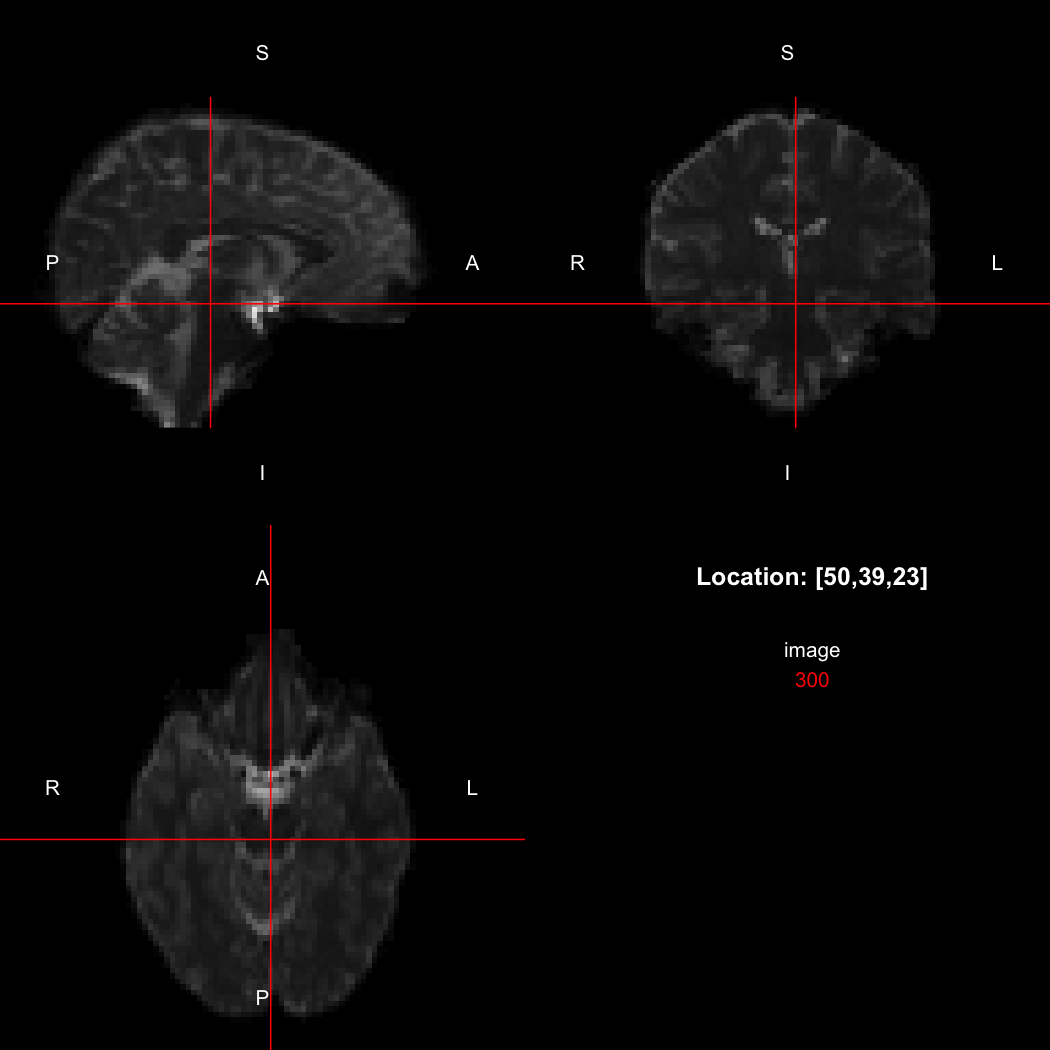

The package contains a basic image viewer, which can be used interactively or noninteractively to examine 2D or 3D images.

view(image)

plot of chunk unnamed-chunk-5

By default, the viewer shows labels indicating image orientation, crosshairs pinpointing the currently selected location, the numerical indices of the current location, and the value of the image at that location. Options allow each of these to be turned off, for the content of the bottom-right panel to be customised entirely, for the colour scale to be changed, and for additional images to be layered on top of the base image. See ?view for details.

So, here, “LAS” means that the positive x-axis points left, the positive y-axis anterior and the positive z-axis superior. This is the so-called “radiological” orientation convention, and can be requested when viewing images for those who are used to it:

view(image, radiological=TRUE)

plot of chunk unnamed-chunk-12

Notice the left (L) and right (R) labels, relative to the view shown above. Setting the radiologicalView option to TRUE will make this the default for all future views.

image[50,39,23]

## [1] 300

## [1] 310

image[47,39,23]

Notice that the sign of the top-left element of the xform has now flipped, and the value of the image at location (50,39,23) has changed because the data has been reordered. The equivalent x-location is now 47, which is the 50th element counting in the other direction (96 - 50 + 1 = 47).